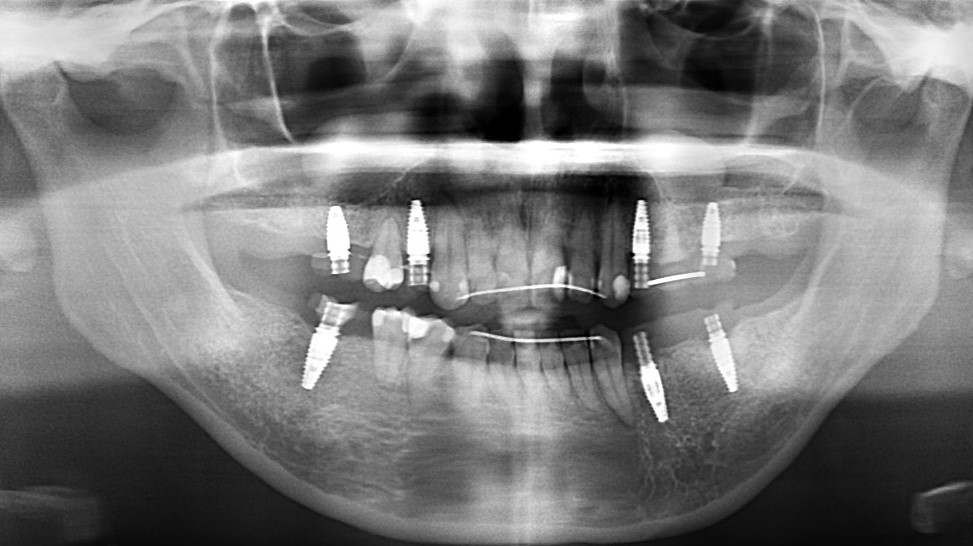

全顎的治療(インプラント+矯正)

臼歯部の根尖病巣と咬合状態の不整があり、全体的な治療を希望。   歯根破折や以前の根管治療時の穿孔などにより、保存不可能な臼歯部を抜歯。   事前にシミュレーションしておいた矯正治療後の歯の並びをもとに、適切な位置にインプラント埋入。   …

2025.12.11